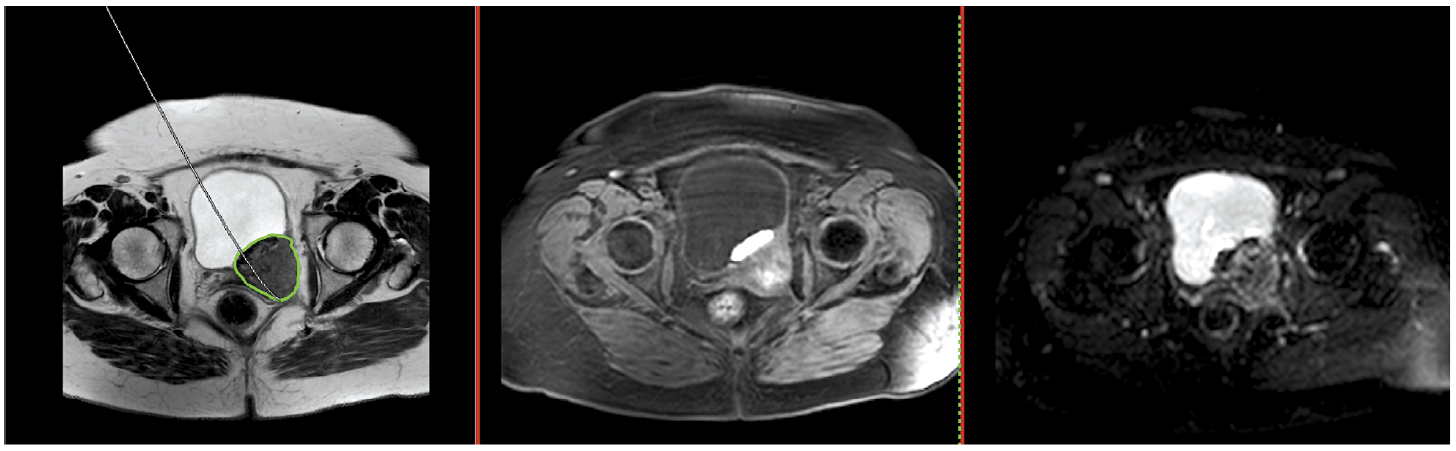

Методы исследования РМП

Существует множество методов визуализации для оценки наличия и распространенности РМП. «Золотым стандартом» визуальной диагностики РМП является цистоскопия [13]. Данный метод применяется для оценки слизистой оболочки мочевого пузыря (МП), устьев мочеточников и уретры. Также одним из относительно недорогих и часто используемых методов визуализации МП без лучевой нагрузки является ультразвуковое исследование (УЗИ) [14]. Для определения локализации и уровня инвазии опухолевого процесса могут применяться как компьютерная томография (КТ), так и магнитно-резонансная томография (МРТ), однако методом выбора считается МРТ [15]. Для оценки опухолевого процесса можно также использовать гибридные методы визуализации, к примеру, позитронно-эмиссионная томография (ПЭТ), совмещенная с КТ (ПЭТ-КТ), и количественная МРТ (диффузионно-взвешенные изображения – ДВИ и карты измеряемого коэффициента диффузии – ИКД) применяются для определения уровня биологической активности и используются в основном для определения стадии и динамики процесса во время лечения (рис. 1) [16–18]. В табл. 1, 2 представлены основные преимущества и недостатки различных методов визуализации образований МП.

Рис. 1. IV стадия РМП с наличием распространения за пределы МП и вовлечением во вторичный процесс запирательных, общих подвздошных, нижних брыжеечных лимфатических узлов и метастатическим поражением легких.

Fig. 1. Stage 4 bladder cancer with invasion and metastasis in obturator, common iliac, inferior mesenteric lymph nodes, and lungs.